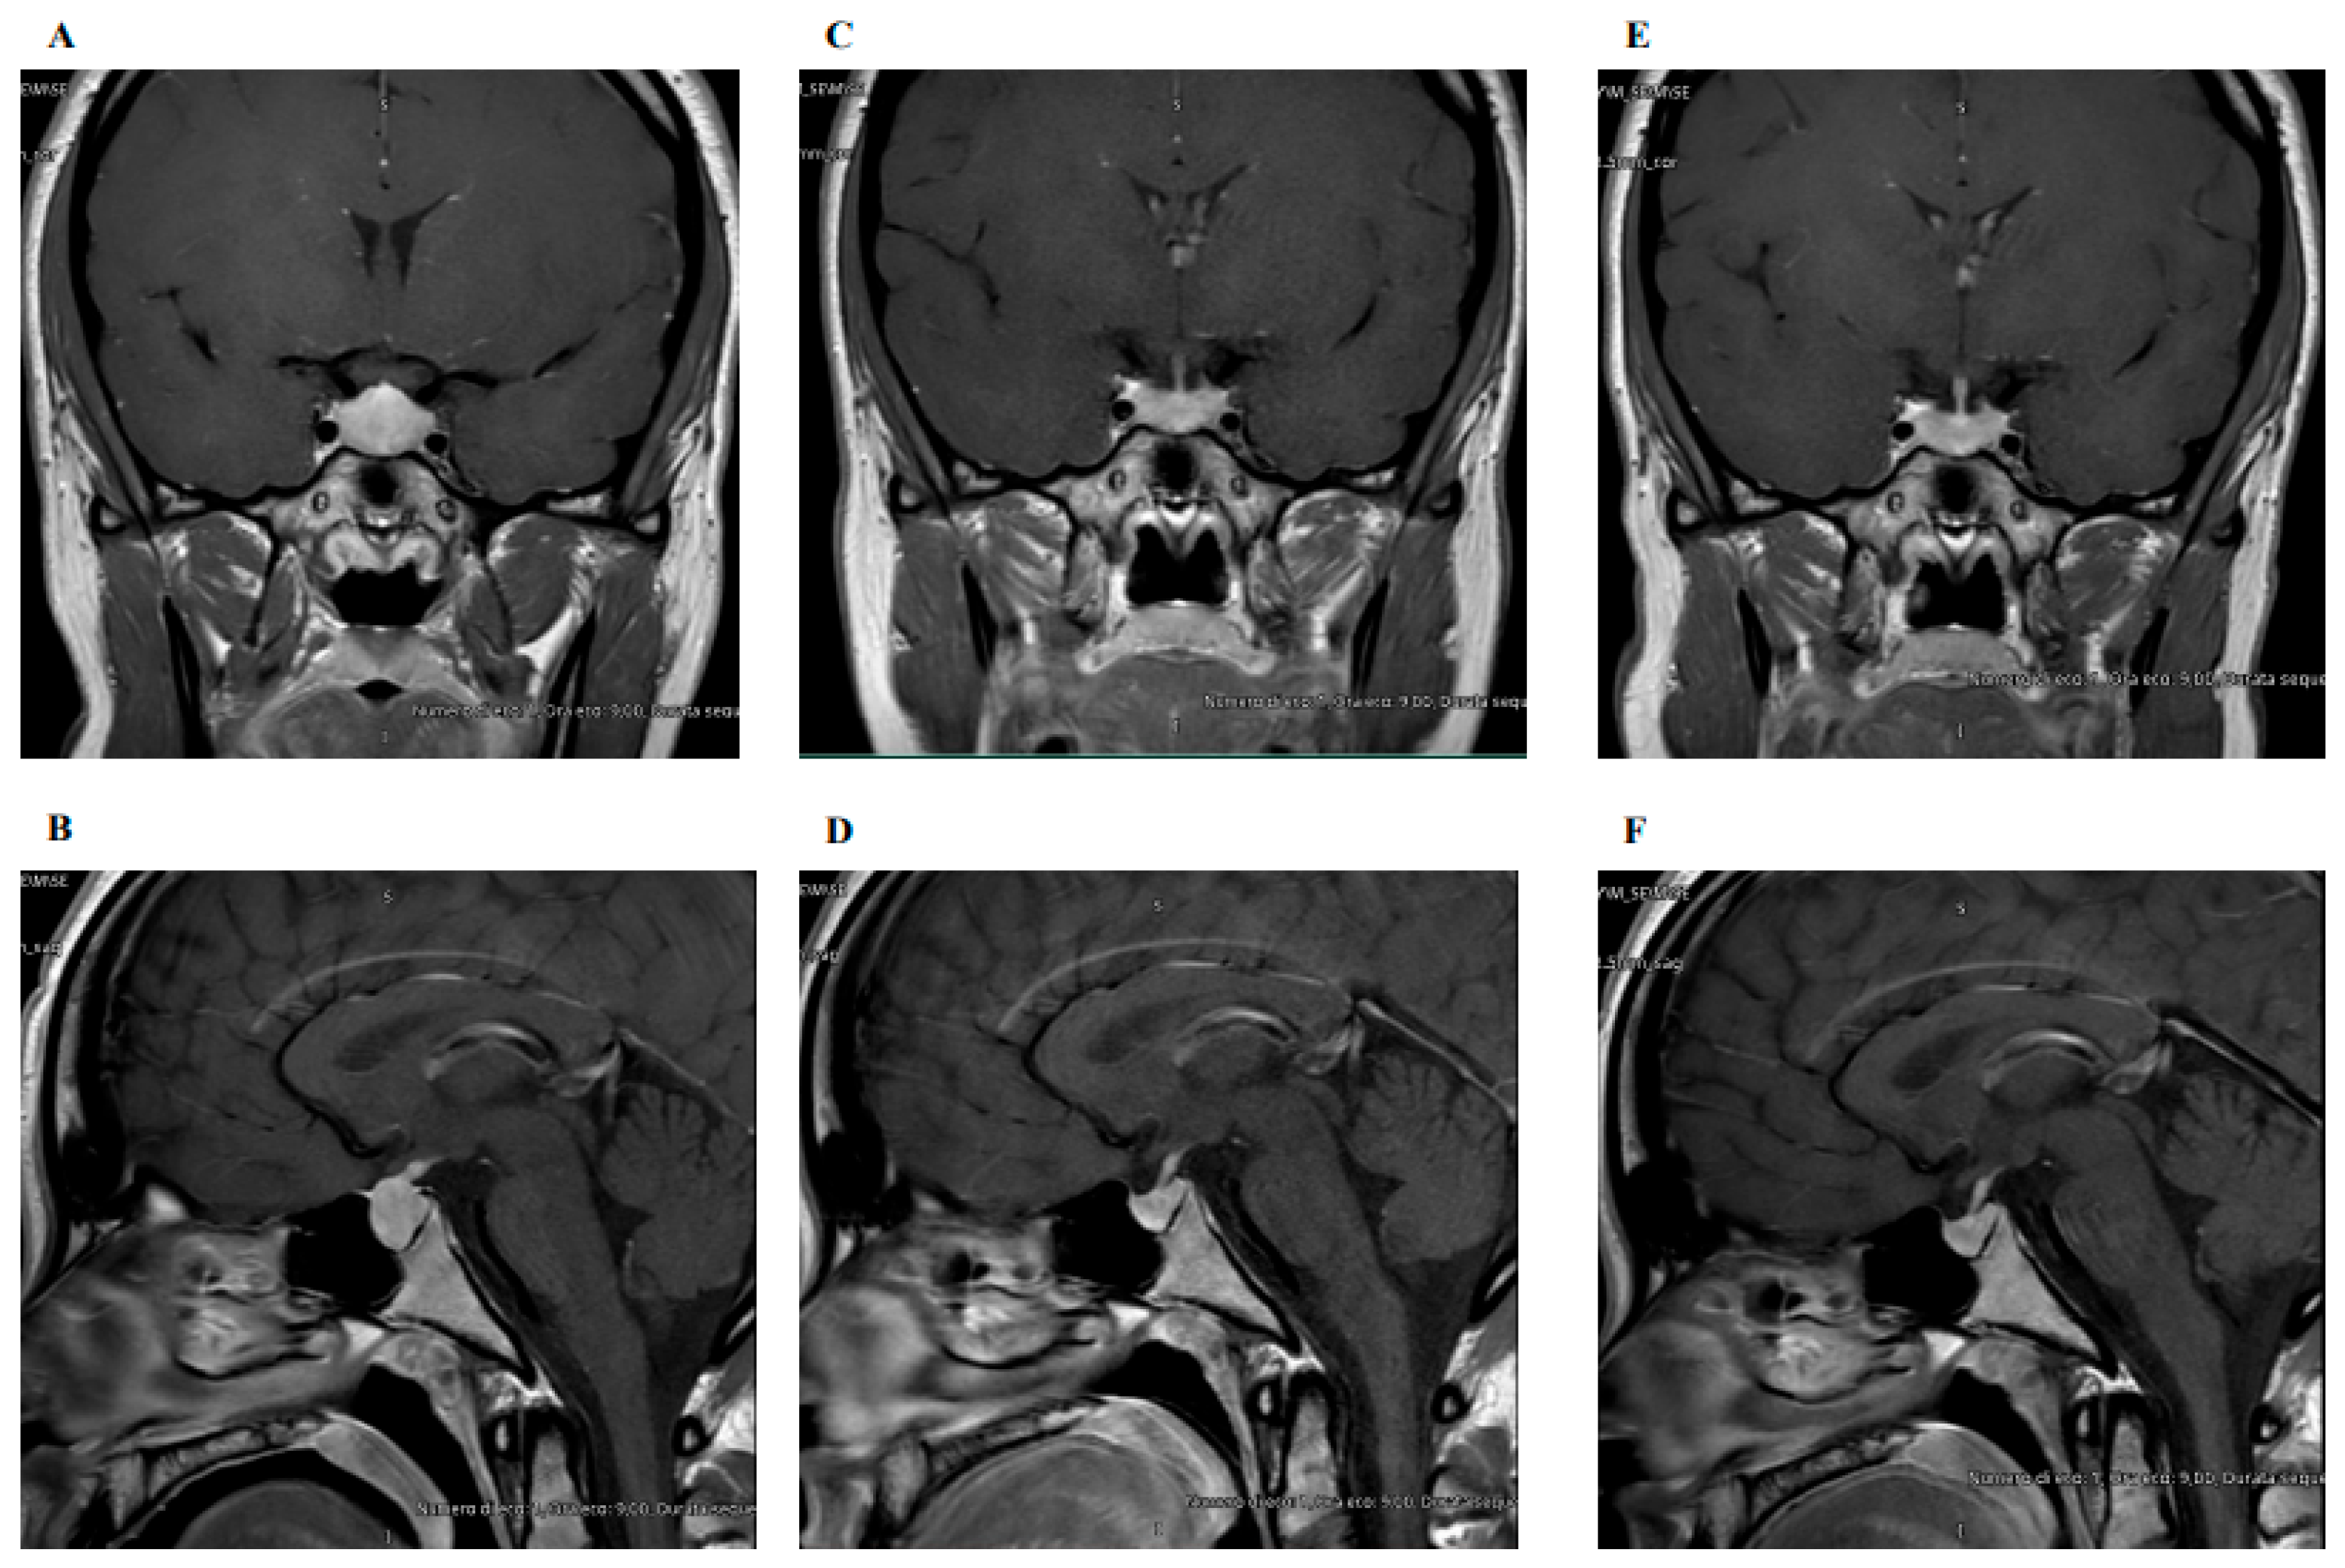

3.1. Case Description

3.2.2. Imaging Features